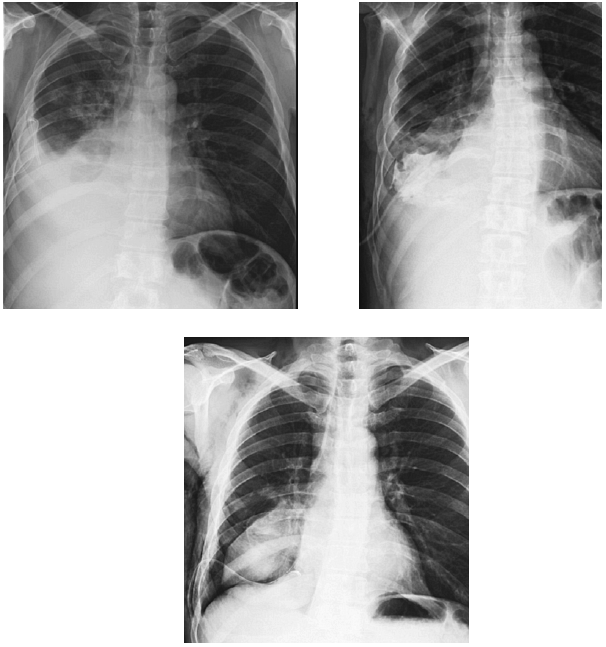

В приемном отделении стационара при осмотре состояние было оценено как тяжелое, выявлен цианоз губ, при аускультации над легкими – везикулярное дыхание, справа в нижних отделах ослаблено, там же выслушиваются мелкопузырчатые хрипы. ЧДД – 20 в минуту. Тоны сердца приглушены, аритмичны. ЧСС – 140 в минуту. АД – 100/60 мм рт. ст. Живот мягкий, безболезненный. Голени пастозны. Выполнена рентгенография грудной клетки, по результатам которой выявлена правосторонняя нижнедолевая пневмония и жидкость в обеих плевральных полостях (рис. 1). На ЭКГ: фибрилляция предсердий с ЧСЖ 120–200 в минуту. Неполная блокада ПНПГ, синдром sI-qIII.

Рис. 1. Рентгенограмма пациента Г. при поступлении в стационар